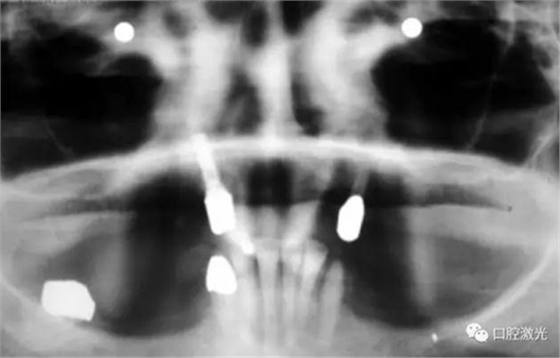

患者女性,43歲。在18年前在13位置上安裝種植體。整個(gè)上顎除23外,牙盡缺失。安裝種植體后,在種植體及23上固定套筒冠義齒。3年后患者發(fā)現(xiàn)刷牙時(shí),臨近13有大量出血現(xiàn)象。通過(guò)探針檢查發(fā)現(xiàn)深度達(dá)6mm。

激光滅菌治療完成后,通過(guò)骨移植手術(shù)完成骨缺失的填充并縫合。一周后可以拆線。在此之后,第6周和第3個(gè)月需要進(jìn)行復(fù)診。最終的對(duì)手術(shù)區(qū)域的檢查確認(rèn)在6個(gè)月時(shí)進(jìn)行。

如今,種植體周圍炎的治療完成已經(jīng)過(guò)去了10多年,上顎義齒的狀況沒(méi)有再出現(xiàn)問(wèn)題。種植體周圍組織基本健康。